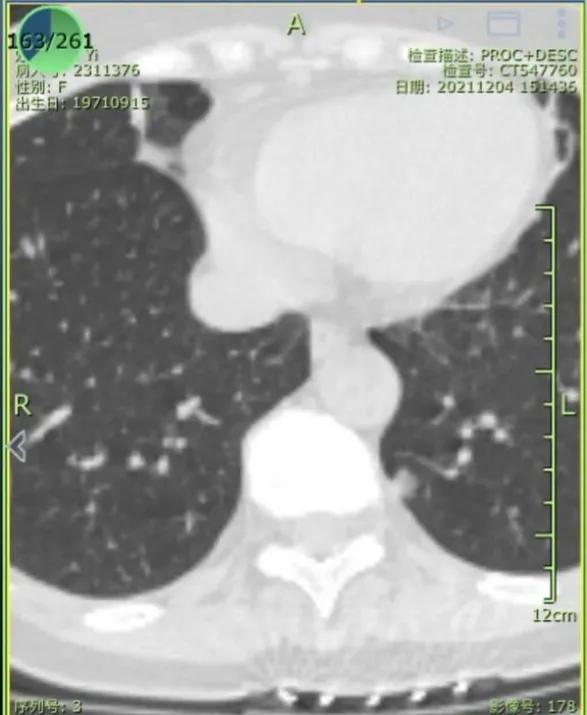

2021年12月,我母亲做CT查出左肺上下叶各有一磨玻璃结节,大小均为6-7mm,医生让3-6月复查。今年6月复查,报告显示有一个侵犯胸膜,大小长至10mm。医生看影像后初判微浸润,让手术切除。慕名而来,恳请戴主任帮忙看看,我们好心安。

一个安徽的宝妈,在6月的时候向我求助:她的妈妈CT查出了两处磨玻璃结节,尺寸都在6-7mm。后来随访过程中发现一个结节增长到了10mm,并且出现了侵犯胸膜的情况,加上省会医生给的一个“微浸润”,这下让这位宝妈异常焦急。再次向我求助,想来重庆新桥进行手术。(插一句,我对宝妈这样质实的孝,异常钦佩;对于宝妈的要求,我一定是安排好所有的绿色通道,亲自处理的)。手术很成功,虽然难度极大(全胸腔粘连),但是考虑到患者未来恢复,和你需要照顾孩子的实际情况,我还是坚持全程微创,没有开胸。手术即治愈,未来慢慢恢复即可,不用担心。

术后您告知,楔切了三个,一个浸润,一个微,一个炎性。我还在抱着侥幸等待大病理,最后大病理结果和术中一致。我希望您看错的愿望落空了,您在贴吧就已经看准了。